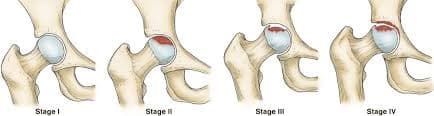

Дунд чөмөгний толгойн үхжил

Тодорхой шалтгааны улмаас дунд чөмөгний толгойд очих цусан хангамж алдагдаж, толгойн хэсэг тэжээлгүй болсноор дунд чөмөгний толгой нь үхжилт бүхий өөрчлөлтөнд ордог түгээмэл эмгэг юм.